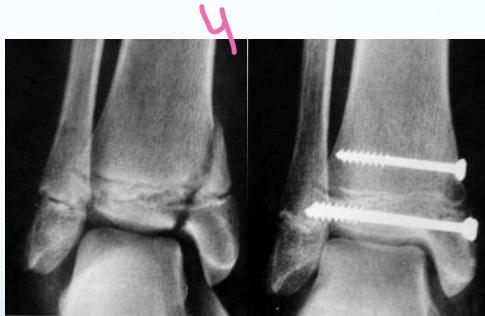

Intra-articular (Type III / IV)

- Anatomical reduction and internal fixation

Case Example: 12-year-old male, Salter-Harris Type II